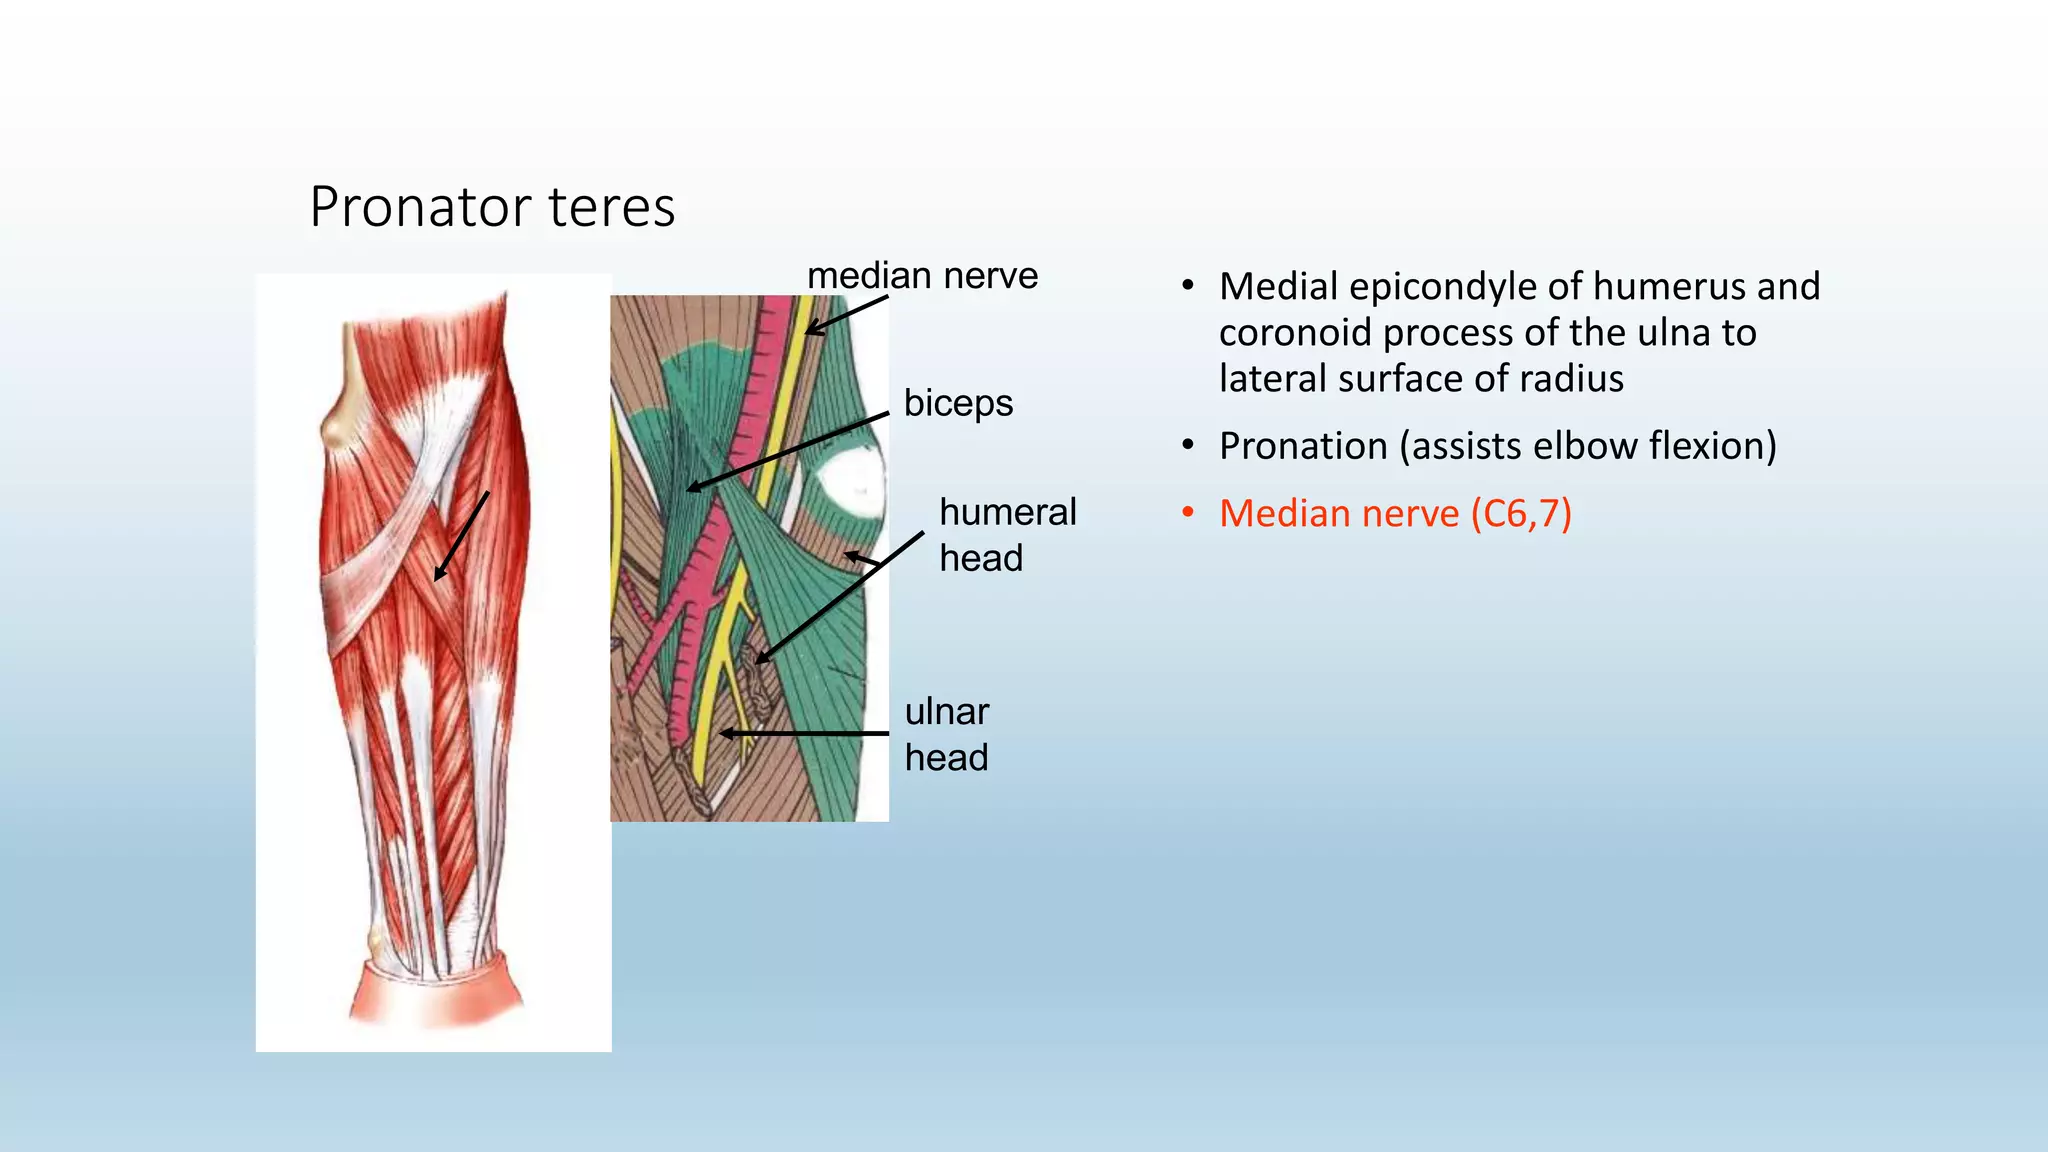

The document summarizes an anatomy revision session on the upper limb. It discusses various muscles of the upper limb including their origins, insertions, innervations and functions. Key muscles covered include the pectoralis major and minor, serratus anterior, deltoid, biceps brachii, brachialis, coracobrachialis, and triceps. It also discusses the rotator cuff muscles and muscles of the forearm including flexor carpi ulnaris and radialis. The session aims to help students identify upper limb muscles and understand their relations to nerves.